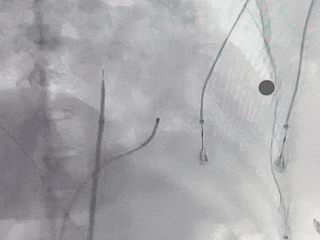

术中房间隔穿刺

确认穿刺位点靠后靠下,使用穿刺针进行穿刺

先进行PFA(脉冲电场消融)